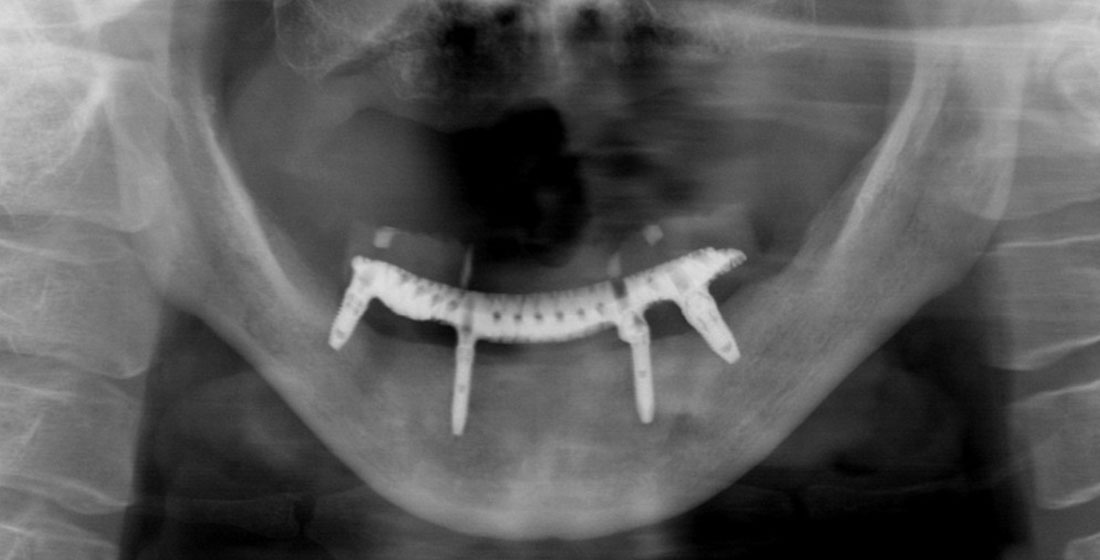

All-on-4症例 Case2

Treatment cases

Before

After

All-on-4症例 Case3